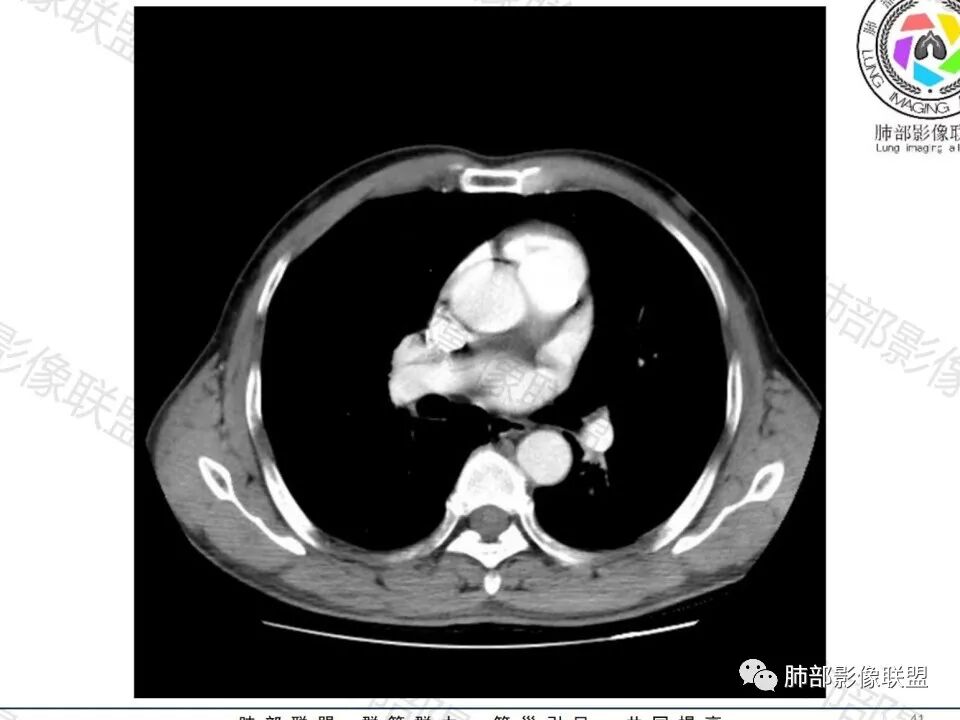

这枚结节的纵隔窗在没有调节窗位的情况下,已经很密实了,说明这个结节里面是软组织的成分,这与普通炎性结节(隐球菌等)的密度还是有区别的,很多年前就有人提出,纵隔窗显示越大,恶性可能越大;

结节周围有磨玻璃影,边界似清不清的,但是总体不如炎性晕征那么模糊;

增强的程度很难讲,但是不均匀强化是可以确定的;

有收缩力,但是很轻,按照常理,实性结节因为有占位效应,不太会有收缩力,但是叶间胸膜有凹陷。所以讲,这个结节还是开了放心。